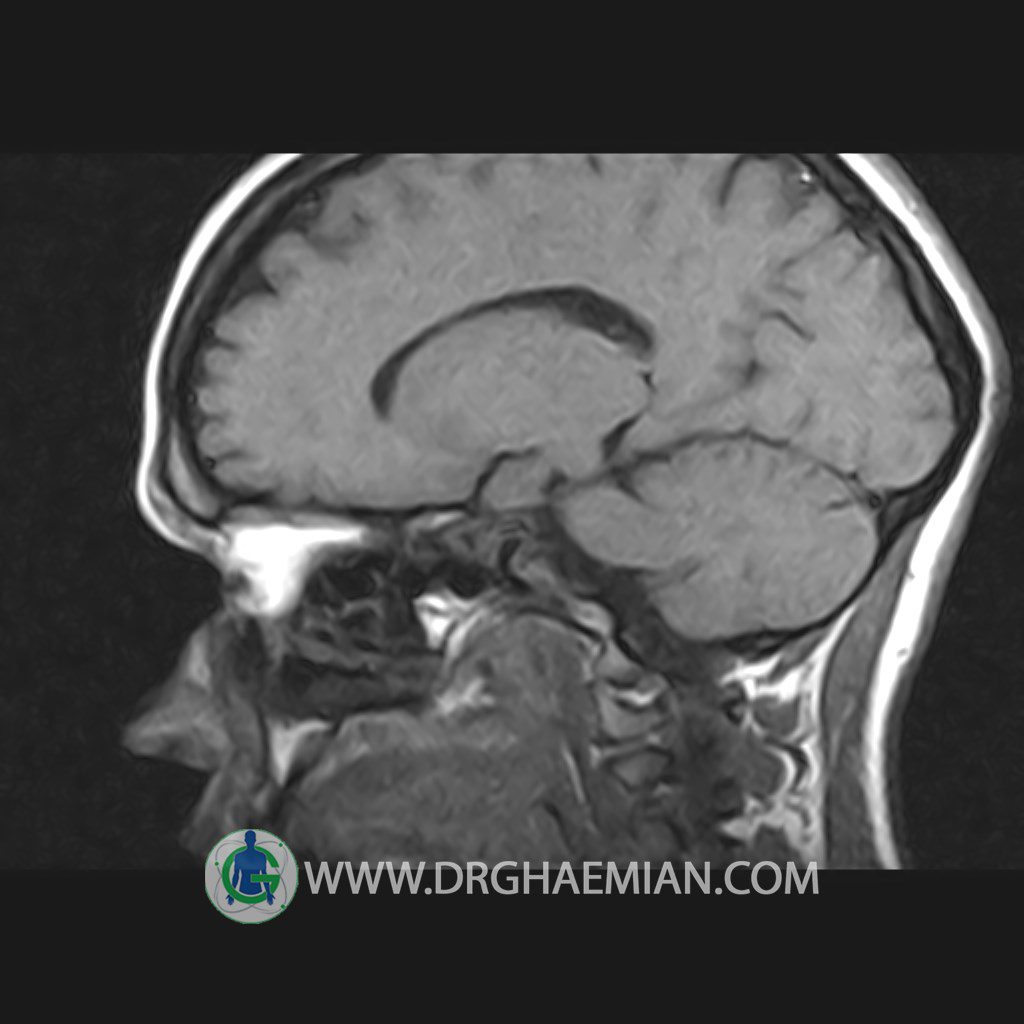

پزشکان اغلب از تصویربرداری ام آر آی برای تشخیص و درمان عارضه های پزشکی که فقط با استفاده از اشعه ایکس یا میدان مغناطیسی و امواج رادیویی قابل مشاهده است، استفاده می کنند. دستگاه ام آر آی تصاویر دقیق از ساختار های داخلی بدن ایجاد می کند. در این کیس هیپرپلازی هیپوفیز و آدنوم مشاهده می شود.

HYPOPHYSIS MRI

(with and without contrast)

Technique: Axial , coronal T1 , Axial , coronal , sagittal T2 , Axial, coronal T1 post Gd & 64 dynamic thin coronal slices.

REPORT :

The sella shows normal size , position and configuration .

The borders of its floor and walls are smooth and sharply defined .

The infundibulum is centered and of normal size .

The optic chiasm and suprasellar spaces appear normal .

The cavernous sinus and imaged portions of the internal carotid artery and carotid siphon are unremarkable .

Evaluable portions of the neurocranium show no abnormalities .

The sphenoid sinus is clear and pneumatized .

– Mild convexity at superior border of pituitary gland with post contrast homogeneous enhancement suggestive for pituitary hyperplasia & iso signal adenoma

is seen